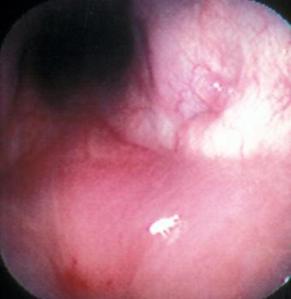

Rinoskopia dhe shplarja e kavitetit nazal janë një vegël e rëndësishme.Një riniskop fleksibel (elastic) futet ne hapesiren nazale.Duke shtyrë me kujdes arrihet të shihet deri ne nazofaringun e pacientit.Disa autore rekomandojne futjen(lëshimin me pak presion) e oksigjenit në kavitet kështu që parazitët migrojnë drejt nazofaringut dhe endoskopit duke bërë të mundur më lehte dallimin e parazitit.

Diagnoza përfundimtare mund të jepet pasi mundim të shohim parazitat ne ednoskopi ose në shplarjen e kavitetit.Gjithsesi kjo nuk na bën të qartë nëse P.caninum është problem primar apo sekondar.